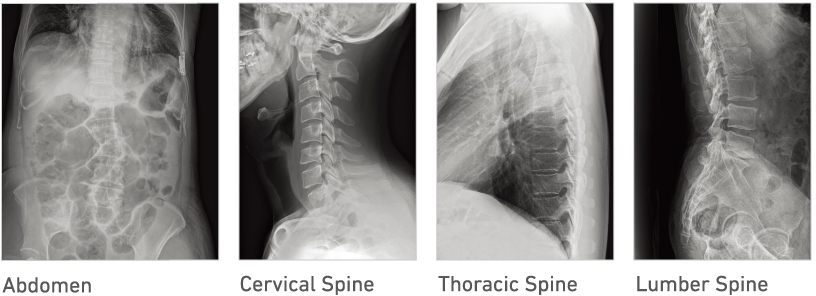

Advanced recognition algorithms automatically adjust contrast and density for individual body parts based on calculation of estimated 3D image data.*5